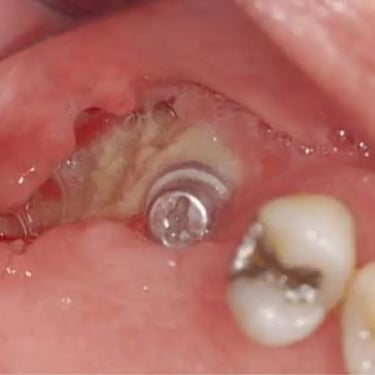

Implantes dentales fracasados

Los implantes dentales fracasados son aquellos que no se han integrado correctamente con el hueso o han desarrollado complicaciones postoperatorias.

Los pacientes pueden notar movilidad en el implante, dolor o inflamación.

El tratamiento puede incluir la extracción del implante fallido y la preparación para un nuevo implante.